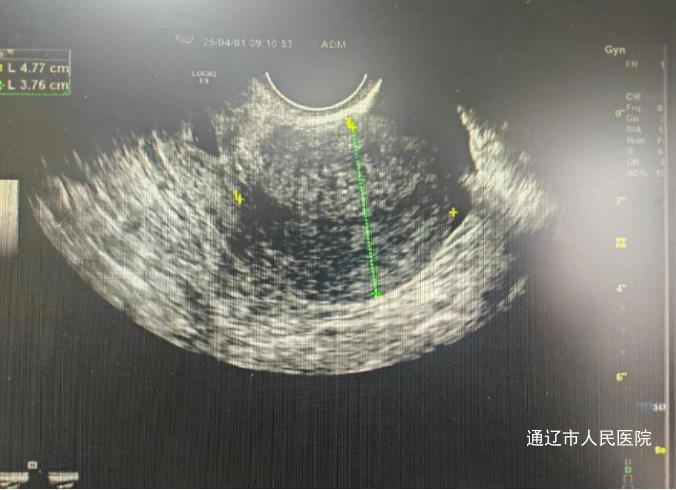

宫颈妊娠因宫颈组织脆弱易引发大出血,严重威胁生命。首例患者为36岁女性,因停经后阴道不规则出血就诊,经检查血β-hCG水平高达5403.8mIU/mL,超声显示宫颈管内异常回声,确诊为宫颈妊娠。另一名27岁患者,因持续4天阴道流血从当地医院转诊,血β-hCG水平达11436mIU/mL,彩超提示宫颈内口妊娠。

确诊后,主任医师李艳春、白鹏来迅速启动多学科会诊,制定腹腔镜下子宫动脉阻断术+宫腔镜辅助下宫颈妊娠组织清除术的治疗方案。妇产科、超声医学科、麻醉科、输血科等科室迅速联动,超声医学科主任吕凤精准定位着床部位,麻醉科医生常红军全程评估风险,手术团队历经数小时紧张操作,成功清除病灶并保留生育功能。术后护理团队密切监测病情,辅以心理疏导,患者血β-hCG水平降至正常,超声显示病灶显著缩小,均康复出院。